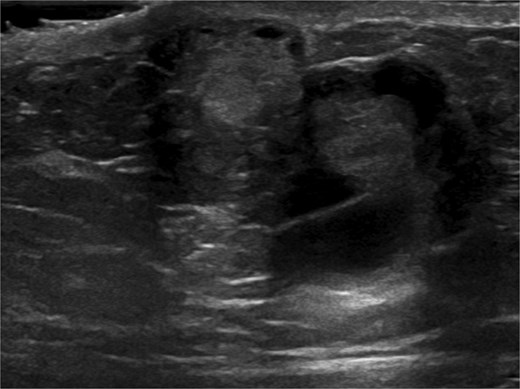

Ultrasound-guided core needle biopsy of the mass showed dissociated fragments of cribriform-like and papillary-like carcinoma (Figs 3 and 4).

Ultrasound of retroareolar area of palpable concern – second view.